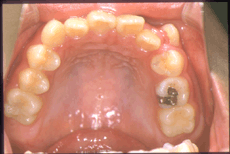

叢生 ソウセイ (別名:乱ぐい歯。八重歯も含む) 症例その1

叢生(別名:乱ぐい歯、八重歯) 矯正治療前

叢生(乱ぐい歯) 矯正治療前 上顎

矯正治療前 上顎